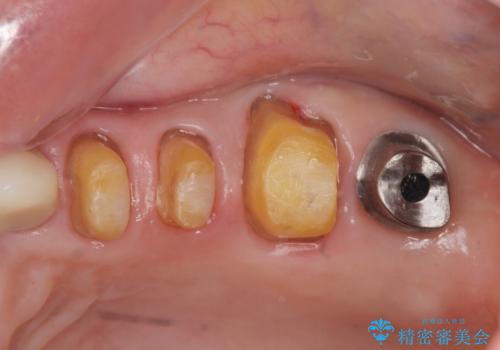

噛み合わせ・歯ぎしりにより、歯周病を発症し感染のコントロール、強い咬合力のコントロールをできるような補綴計画をたてます。

- 61万円(仮歯・フルジルコニアクラウン×4 ・インプラント・チタンカスタムアバットメント )費用は治療当時の料金となります

分岐部病変を併発していた歯は、抜歯としインプラントによる咬合機能の回復。残すことのできる歯は歯周治療後連結補綴を行い歯ぎしりに対抗します。